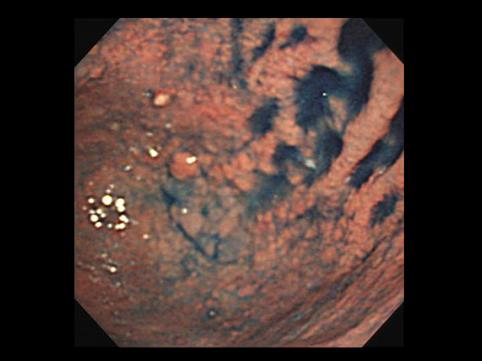

Criteria of Hist.ClassificationMalignant epithelial tumor/Adenocarcinoma

LocationStomach/More than one of above

Technique, MethodEndoscopy

Macroscopic TypesType 0/IIb (IIb+IIa) Superficial flat and elevated type

Size40 -

Depth of Tumor Invasionmucosa